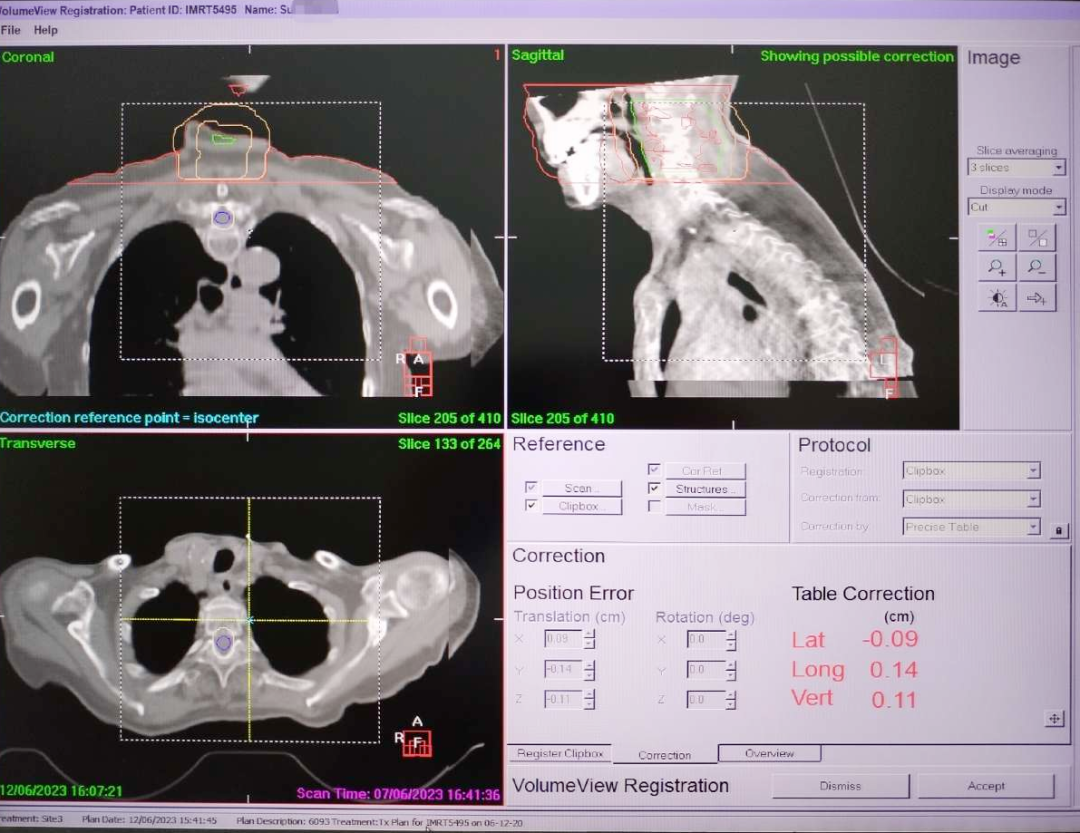

患者,女,88岁,诊断为肺癌颈椎转移,临床表现为颈椎疼痛及活动不便。首次定位时患者配合度较好,采用传统的热塑体膜联合固定体架定位,在等待治疗期间,患者情绪发生变化,延误治疗进程,不愿配合治疗。一周后患者及家属决定继续治疗,但是随着病情的进展,摆位时患者颈部疼痛增加,情绪紧张,不能配合完成治疗。面对患者的特殊情况,放疗医师、物理师与技师经多方面分析,及时与患者家属沟通,决定改用真空负压袋联合体部固定装置技术,为患者快速完成二次定位。真空负压袋能够根据体型与人体轮廓快速成型,具有适形度高、躺卧舒适度高的特点,目前在特殊体位患者中应用具有优势。患者改用真空负压袋固定技术后,躺卧舒适度改善,表现出配合治疗的意愿,体位保持良好,位置精确度提高。经两周治疗之后,患者疼痛症状明显减轻,患者及家属对个性化定位技术的应用表示认可和满意。